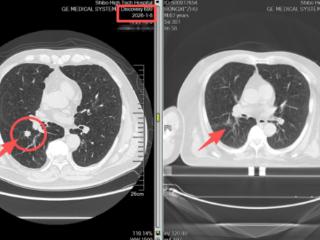

两周消融肺结节——淄博世博高新医院射波刀“精准狙击”守护肺部健康